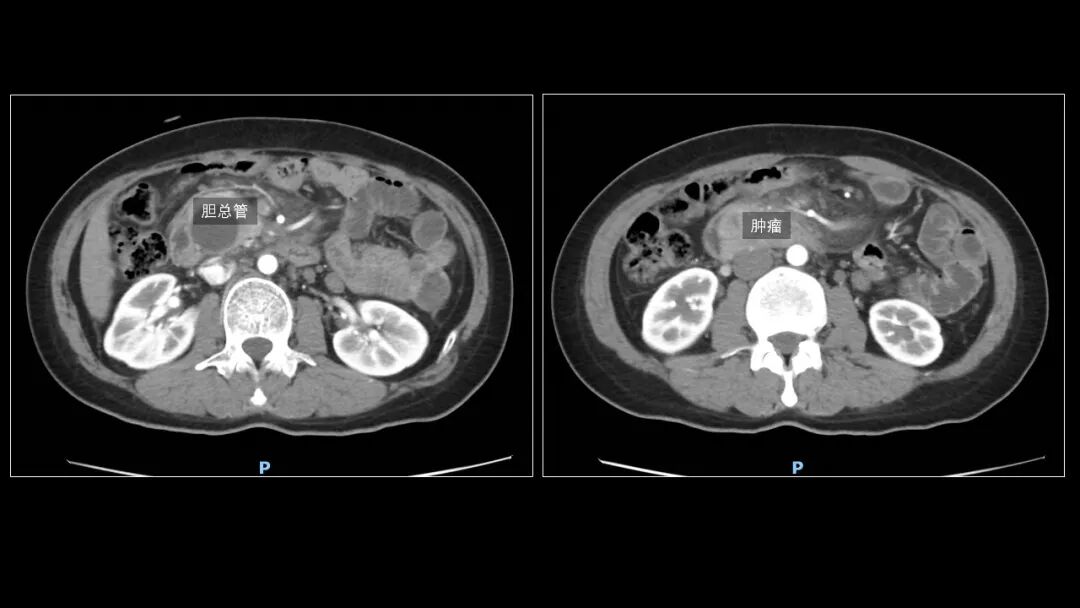

“胆总管下段显示不清,可疑软组织密度影在其内,同时还伴有肝内外胆管的扩张及胰腺炎表现;上腹核磁提示壶腹部有一个肿块,肝内外胆管显著扩张,胰管也有增宽,考虑壶腹恶性肿瘤……”

壶腹占位

是导致背痛和尿色深黄的主要原因

可能得了非常严重的恶性肿瘤性疾病

△胡女士拍片结果